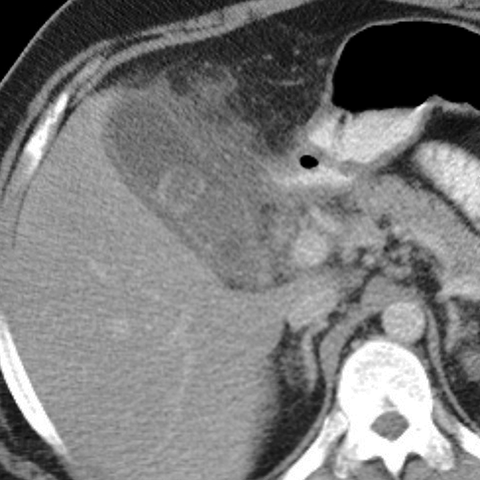

Acute Cholecystitis, CT [1 of 2]